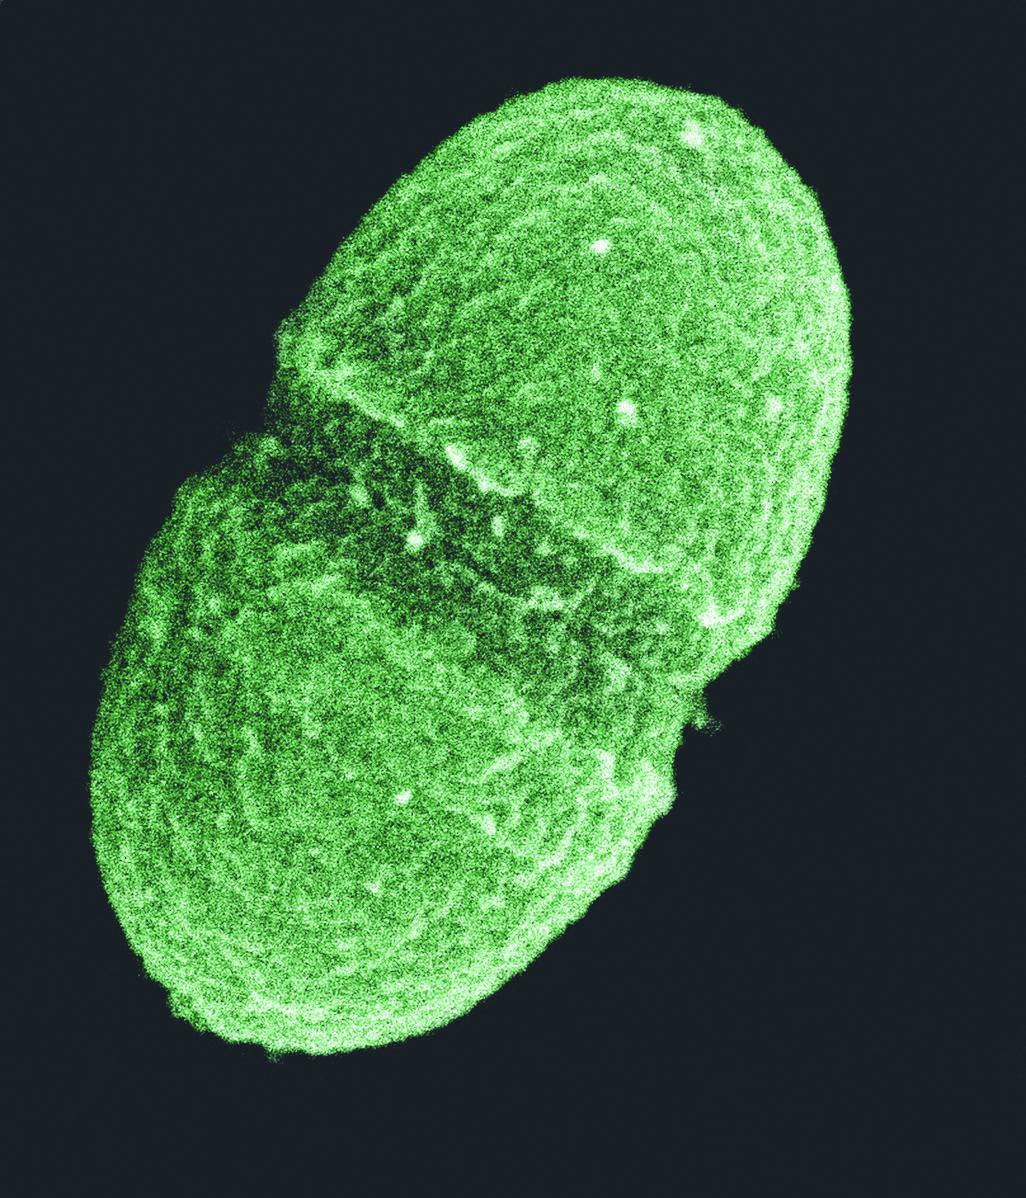

耐甲氧西林金黄色葡萄球菌(MRSA)是一种金黄色葡萄球菌,但此菌株对许多抗生素皆有耐药性。

耐甲氧西林金黄色葡萄球菌是最恶名昭彰的超级细菌。普通的金黄色葡萄球菌是种常见的细菌,常会无害地出现在皮肤上,这种菌在20世纪50年代开始对抗生素产生抗药性,但MRSA则到1962年才出现。